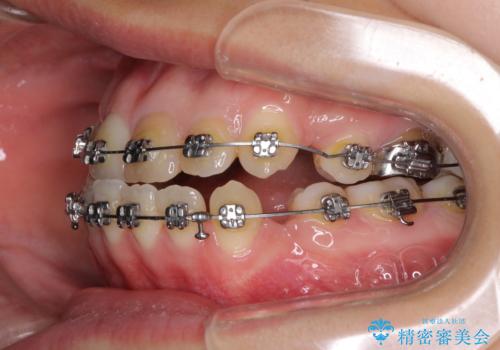

- 矯正装置

- メタルブラケット

- 治療期間

- 2年6ヶ月

- 治療回数

- 10-30回